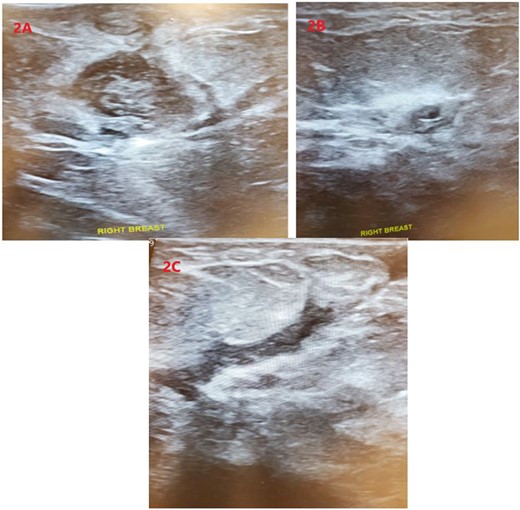

Upon physical examination, the patient was found to have multiple red, indurated and tender areas on her right breast with concerns for a fistula to the lateral aspect of her nipple as demonstrated in Fig. 1. A sonogram was performed in the office identifying multiple abscess cavities with confirmation of a fistulous tract as shown in Fig. 2A–C. The patient had two aspiration procedures of her fluid collections with the initial set of wound cultures that were not successful in isolating an organism. Her infection did not resolve with further penicillin administration. Concerns for multidrug-resistant organisms and acid fast bacilli were included in the differential diagnosis.

Sonographic imaging of the right breast identifying two complex fluid collections (A) and (B) at the 3:00 position. (C) Showing a fistula tract.